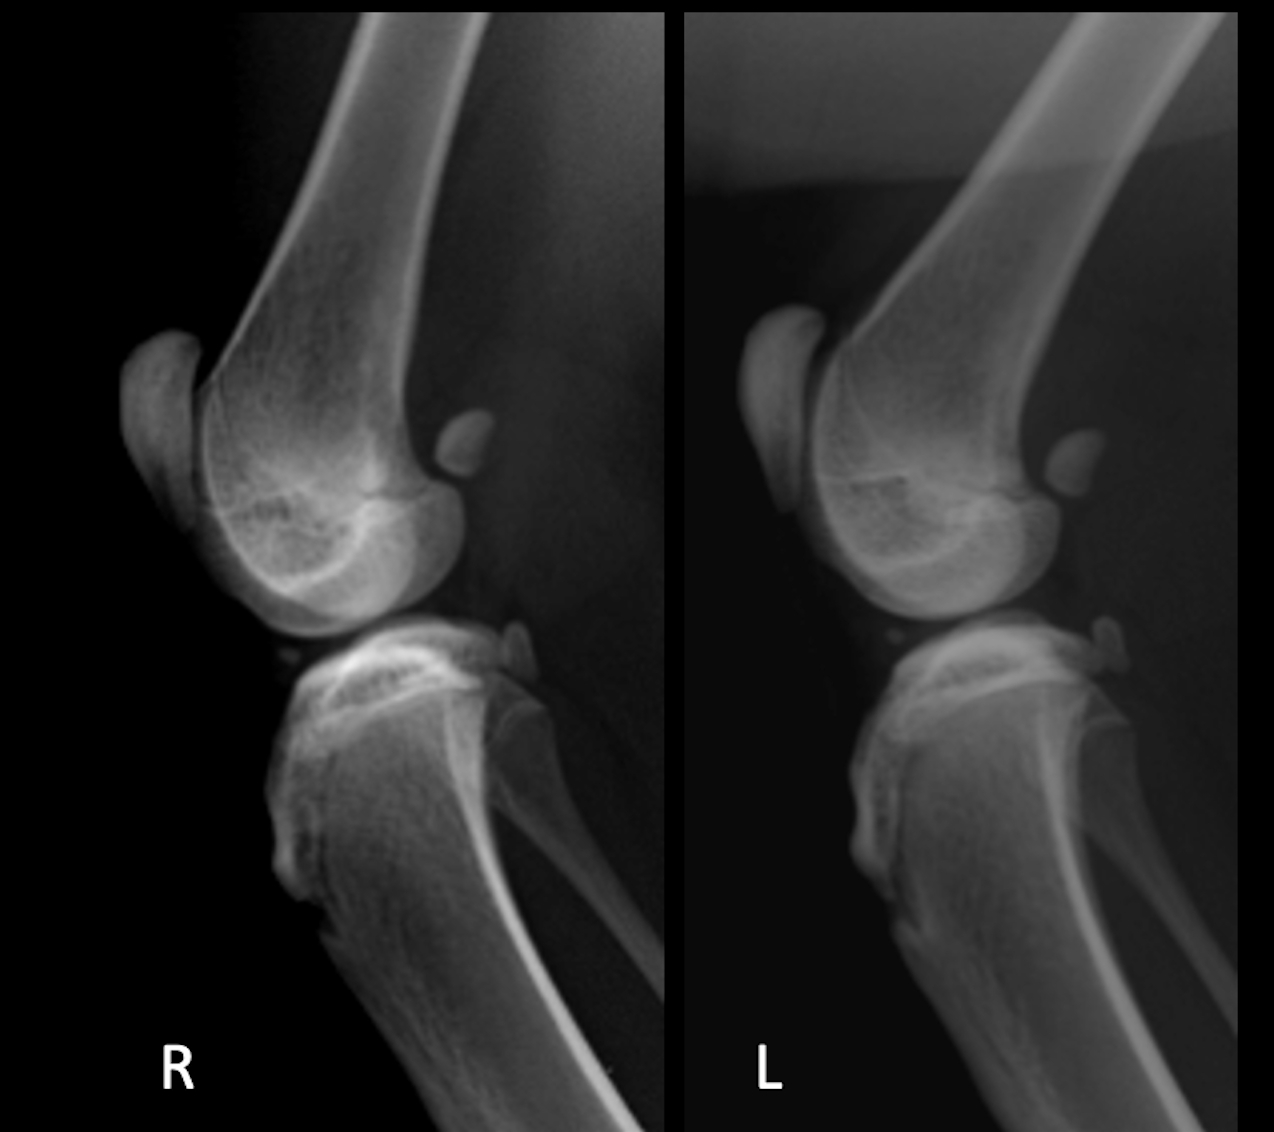

整形・神経外科

整形外科および神経疾患は、生活に大きな支障をきたします。

特に近年、小型犬や猫の飼育割合が増え犬種猫種的な疾患(膝蓋骨脱臼や骨軟骨異形成症など)も多く、怪我などによる靭帯損傷にも遭遇します。

当院では骨折、靭帯損傷などの外科治療以外にも免疫介在性関節炎など内科的な治療が必要な整形疾患も対応しております。

また、神経疾患では椎間板ヘルニアに対する、内科および外科治療にも対応しております。

主な症状

膝蓋骨脱臼や股関節脱臼、前十字靭帯損傷、無菌性大腿骨頭壊死症(レッグ・カルベ・ペルテス病)、免疫介在性多発性関節炎、変形性関節症、椎間板ヘルニアなど